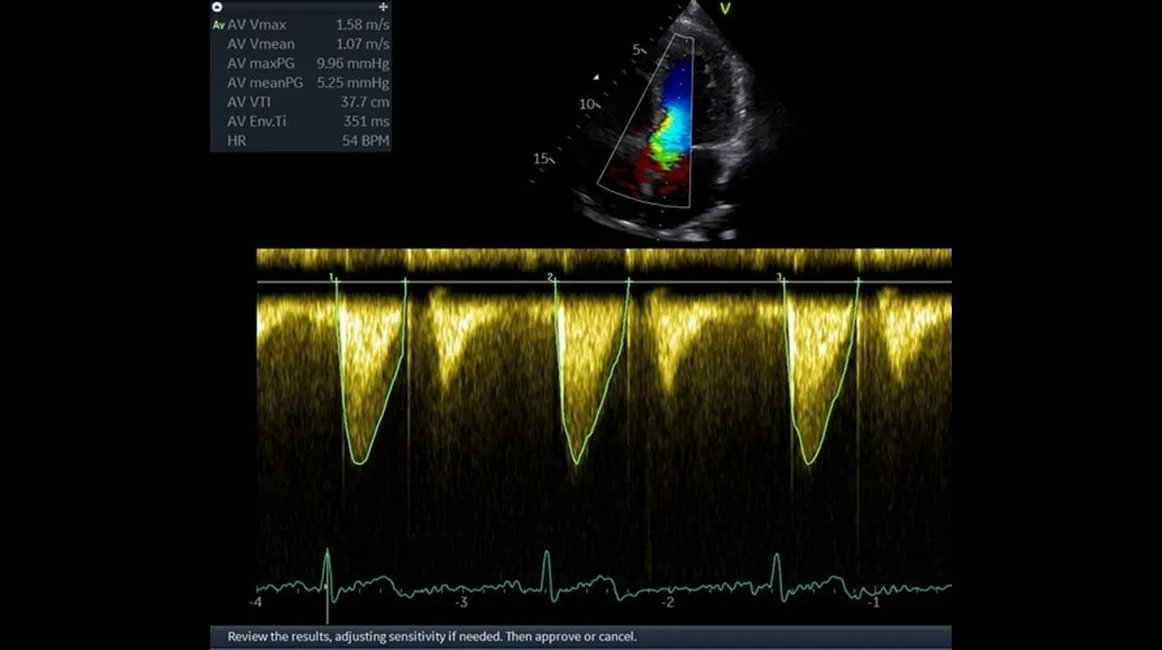

| Импульсно-волновой допплер (PW) | Спектральный анализ локальных потоков для количественной оценки скоростей и расчёта градиентов давления. |

| Непрерывно-волновой допплер (CW) | Измерение высокоскоростных потоков при клапанных пороках и других кардиологических патологиях. |

| Режимы визуализации | 2D, M-режим, анатомический M-режим, цветовой и энергетический допплер, импульсно- и непрерывно-волновой допплер, TDI/TVI, расширенные кардиологические режимы (strain, AFI и др.) |

| Strain / AFI | Режимы деформационного анализа миокарда (Global/Segmental Strain, AFI) для раннего выявления нарушений сократимости. |